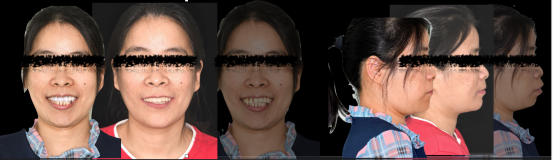

即刻修复后患者的正侧貌美学评估:

正貌美学评估:

· 面部对称、三等分,面中线与中切牙中线一致,上下唇可自然闭合。

· 侧貌美学评估:

· 上唇丰满度:适中,鼻唇角105°,上下唇位于美学E线,直面型。

· 预告面型及修复后与修复前对比,患者的正侧貌美学得到了极大的改善,凸面型变为直面型。

· 修复体红白美学满意,前伸侧方咬合均无干扰,前牙前突问题解决,指导患者清洁。

· 重度牙周炎伴上颌前突患者,通过数字化正侧貌美学预告,指导数字化排牙,预先制作的临时修复体,通过士卓曼360数字化序列导板成功的在术后即刻恢复患者的咬合关系。

· 应用士卓曼360数字化序列导板+预成临时修复体,能够全方位成功辅助重度牙周炎伴上颌前突患者实施即刻种植即刻修复。术后即刻获得可预期的美学和功能效果!

治疗前

治疗后